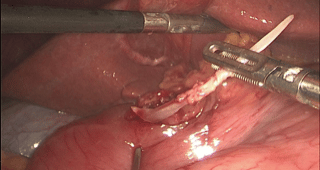

△普外科與消化內(nèi)科共同為王先生取魚刺

手術中

救治團隊使用胃鏡發(fā)現(xiàn)

魚刺已穿透胃壁

腫脹的粘膜將魚刺完全蓋住

已經(jīng)無法通過胃鏡取出

△魚刺已經(jīng)完全穿透胃壁,胃鏡下無法觀察

△取出魚刺

救治團隊立即調(diào)整方案轉(zhuǎn)行腹腔鏡微創(chuàng)手術術中探查發(fā)現(xiàn)患者胃竇部小彎側(cè)胃壁水腫增厚有一根5cm*0.3cm*0.3cm長的魚刺穿破了胃壁小心翼翼將異物取出后手術團隊修補了穿孔區(qū)術后王先生病情穩(wěn)定目前已平穩(wěn)出院

△魚刺長達5cm